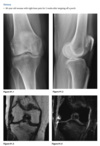

Anteroposterior (Fig. 2.16.1) and lateral

(Fig. 2.16.2) radiographs of the left knee show a semi-

circular lucency, with an adjacent bony fragment,

on the lateral aspect of the medial femoral condyle

(arrows).

sagittal T2-weighted MR

image in the same patient demonstrates minimal

linear increased signal intensity in the same region

as the lucency, located between the subchondral

bone and the fragment (Fig. 2.16.3, arrow). The frag-

ment has low signal intensity and is not completely

covered by cartilage.

Osteochondritis dissecans (osteochon-

drosis) of the medial femoral condyle

from an osteochondral fracture

that was initially caused by shearing, rotatory, or

tangentially aligned impaction forces.

The presence of linear high T2-weighted

signal intensity between the fragment and donor site

indicates fluid or granulation tissue and strongly sug-

gests instability of the fragment (i.e., loose in situ

fragment) (Fig. 2.16.4, arrowheads). Focal cystic areas

beneath the fragment or denudation of articular carti-

lage are also MR signs suggesting an unstable fragment.

All patients with radiographic evidence of osteochon-

dritis dissecans could potentially benefit from MRI to

assess the integrity of the donor fragments before any

surgical or arthroscopic intervention or therapy (71).